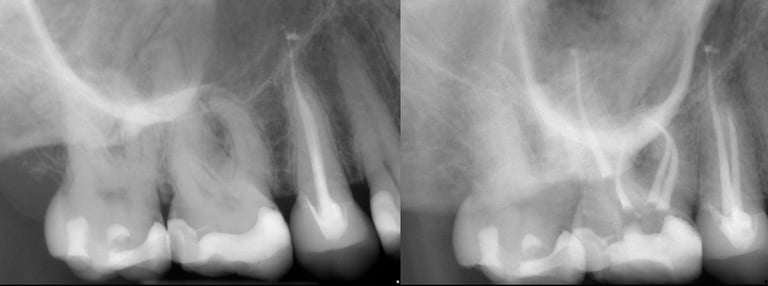

Gallery 1: Initial Cases

Initial Root Canal Cases with preoperative and postoperative radiographs.

#5 RCT with 3 canals

#2 RCT with 4 canals